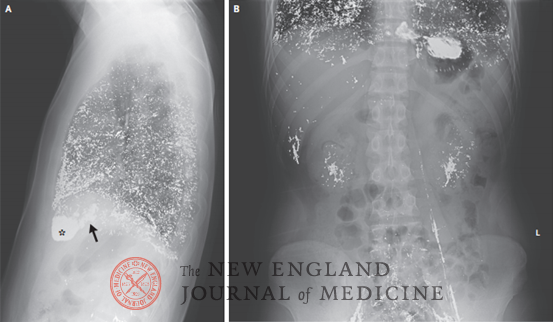

一名既往健康的25岁男性因逐渐加重的疲劳、恶心和干咳3个月而至内科综合门诊就诊。在症状出现前1周,他根据股癣的民间疗法,静脉内注射了4 mL汞。查体发现结膜苍白。实验室检查显示,血红蛋白水平为6.5 g/dL(参考范围:12.0~16.0),血清汞水平为430 μg /dL(21,440 nmol/L;参考值<1.5 μg /dL [70 nmol/L]),24小时尿汞水平为29,792 μg(148,510 nmol;参考值<45 μg [220 nmol]),且肾功能正常。胸部X线检查(图A)显示肺部、右心房(箭号)和右心室(星号)弥漫性分布不透明金属影。腹部X线(图B)显示肝脏、肾脏、髂静脉和左性腺静脉可见类似金属密度影。该患者被诊断为汞中毒。患者收入院,并开始静脉内注射二硫基丙醇磺酸进行络合剂治疗。经过2周的治疗,患者的症状有所缓解,血红蛋白水平升高到8.0 g/dL,血清汞水平降至254 μg /dL(12,660 nmol/L)。该患者出院,医生建议继续口服二巯基丁二酸进行络合治疗。